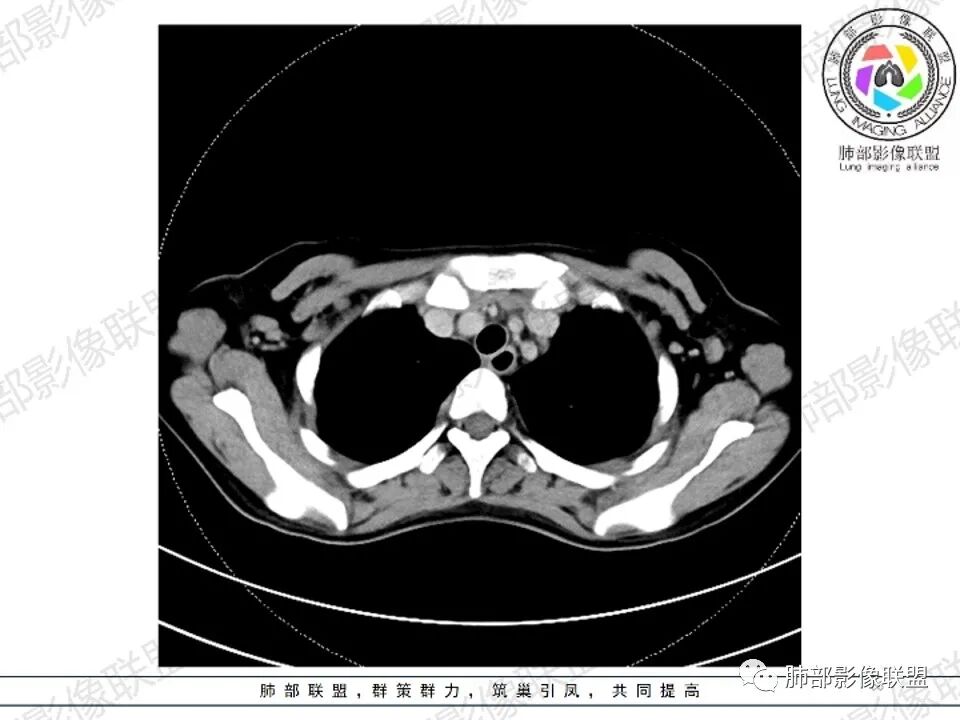

2.影像显示前纵隔不规则块状影,依势贴附心脏大血管旁,密度不均,边界不甚清楚,有结节融合感。

3.病灶轻度不均匀强化,可见血管穿行,散在液性低密度区。

双肺门未见肿大淋巴结。

4.双侧腋窝区见增大淋巴结,边界清楚。